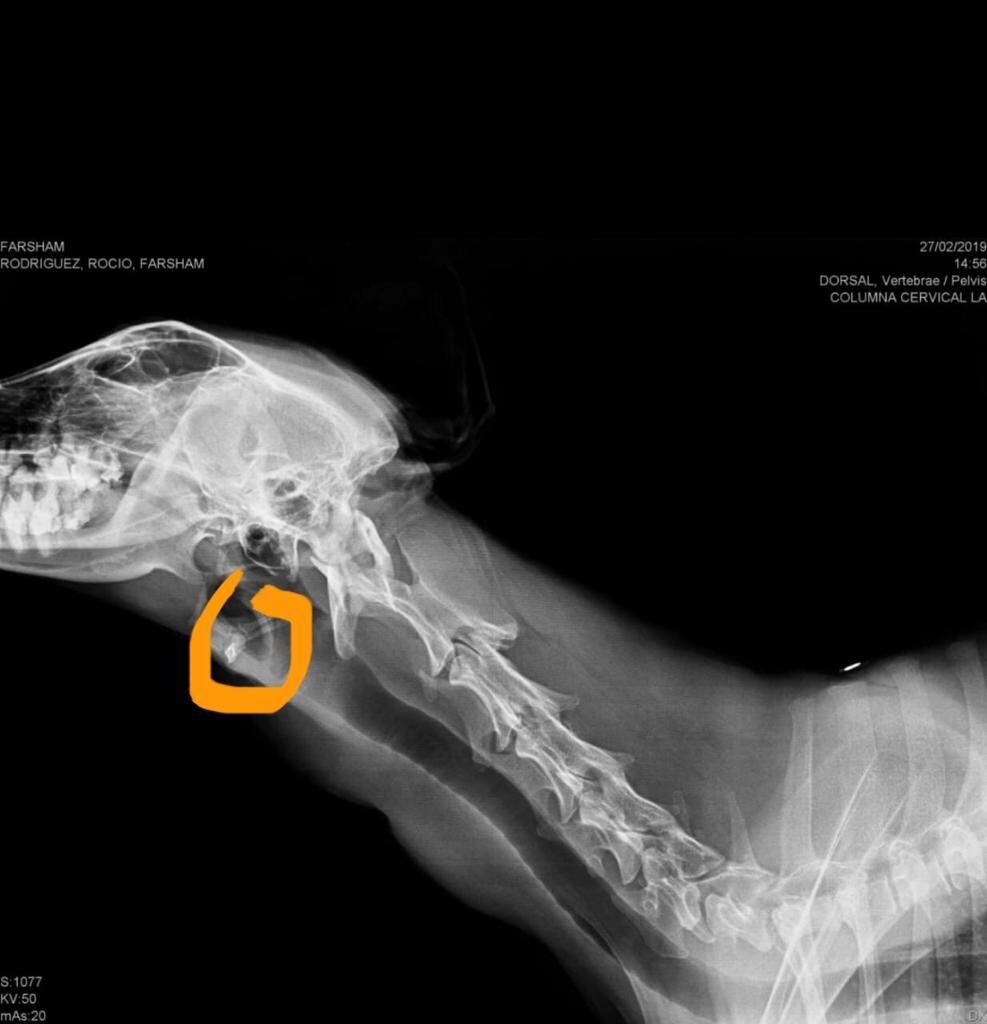

A esta mascotica le apareció una pelotita en el cuello hace cinco meses que resultó ser maligna.

“Este año lo llevé a que una veterinaria lo desparasitara y ella detectó la pelota al lado izquierdo del cuello, le salió muy rápido. Resultó ser un cáncer de tiroides, muy semejante al del humano”, contó su mamá Rocío Rodríguez.

"Cuando lo llevé a hacerle placas, le dieron una semana de vida, eso fue en febrero de este año. Bajó mucho de peso. Y entonces lo llevamos a acupuntura, algo que lo estabilizó bastante porque tenía mucha diarrea. Luego nos comentaron sobre la quimioterapia y encontramos a la doctora que la aplicaba", contó Rocío.

“Ha estado bastante bien, hemos logrado estabilizarlo, la masa en el cuello se mantiene del mismo tamaño, lo cual es bueno; la masa en el pulmón, donde tenía metástasis, también está igual. Hemos logrado estancar la enfermedad para que pueda seguir con su vida normal, ha aumentado de peso y está con buen ánimo. Luego de culminadas las sesiones lo monitearemos una vez al mes”, explicó García.